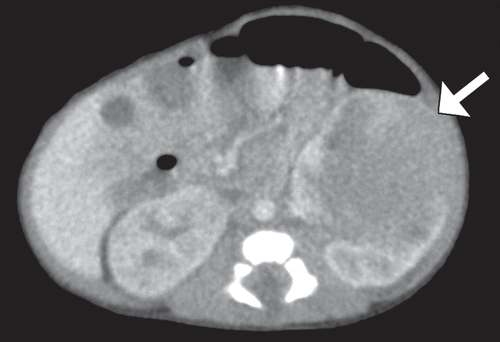

Newborn with a hypoechoic lesion on ultrasound

A

MESOBLASTIC NEPHROMA.

Wilms like tumor, but <1 month old.

Solid renal tumor of infancy. Fetal hamartoma. Most common renal tumor in the first month of life.Involves renal sinus.